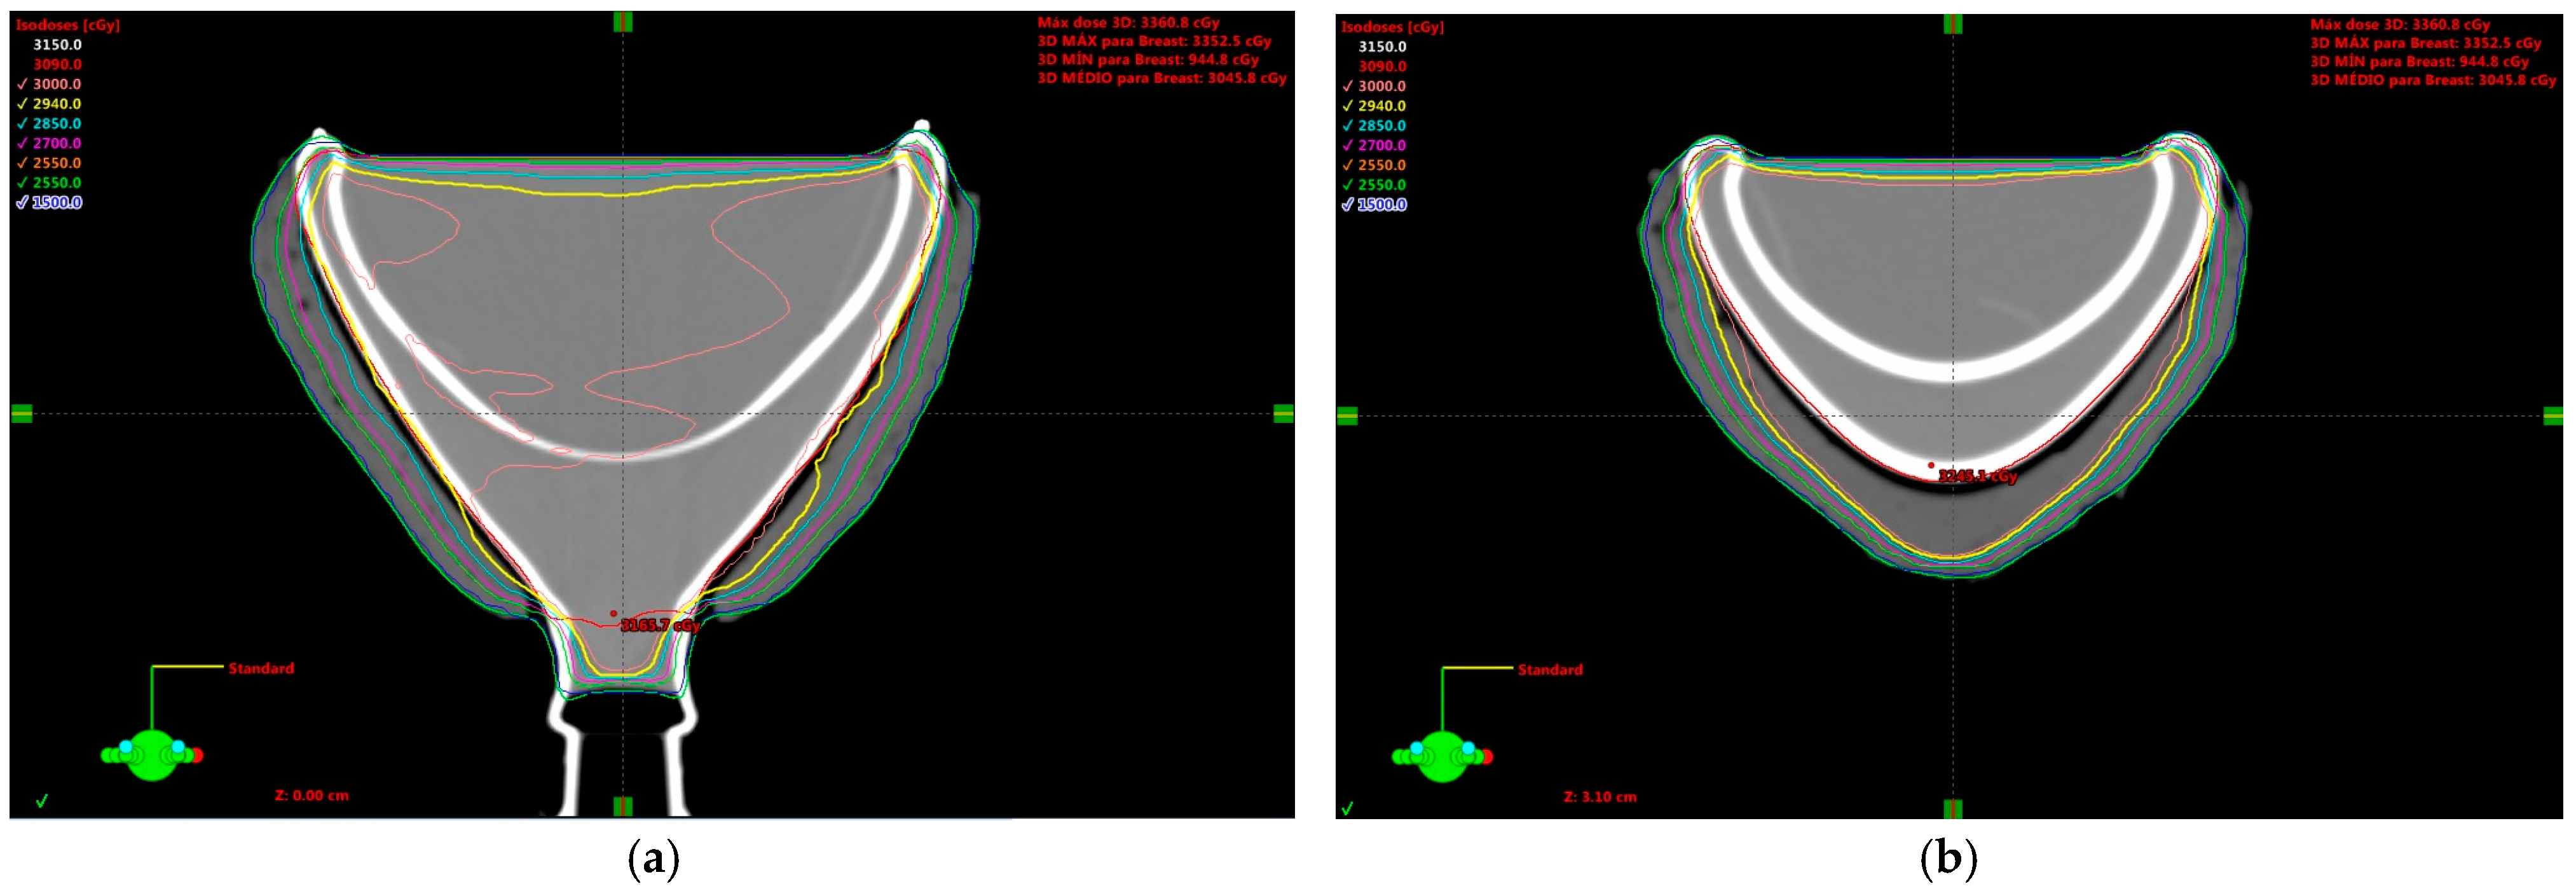

2. Results and Discussion